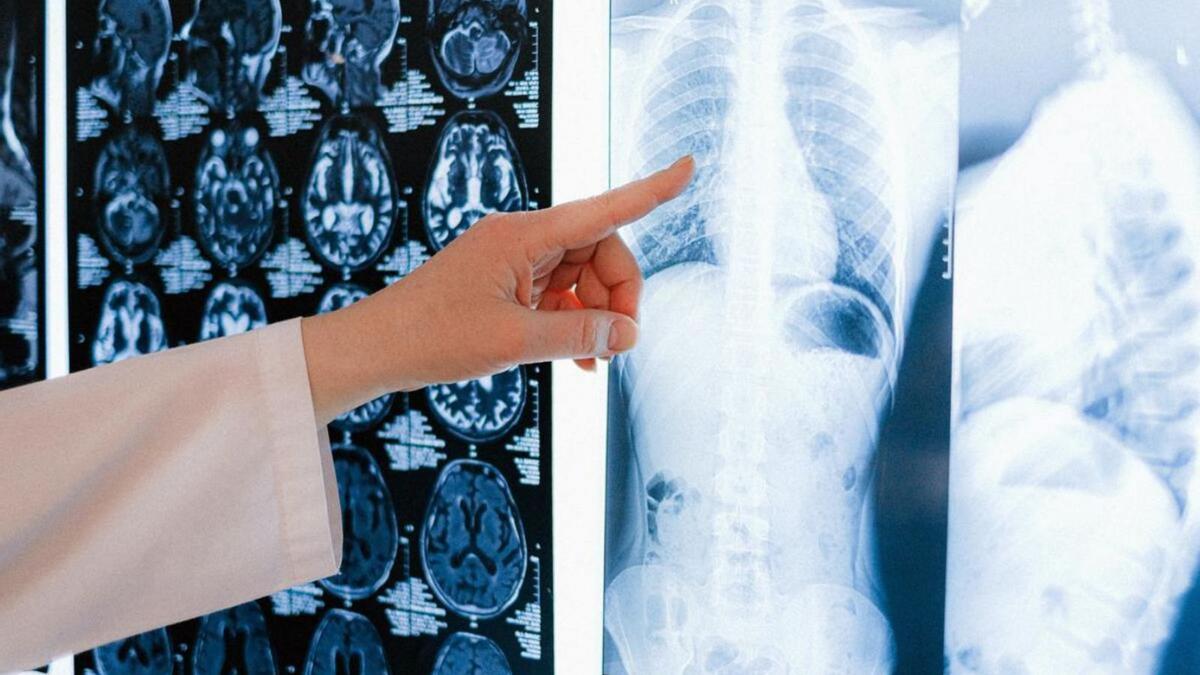

Cassandra es un programa multicéntrico y multidisciplinar que incorpora la Tomografía Computarizada TC de baja dosis de radiación como herramienta de cribado, en combinación con la deshabituación del tabaco y la colaboración con Atención Primaria. El proyecto pretende aportar evidencia sobre la factibilidad del cribado de cáncer de pulmón en nuestro país ayudando de esta manera a que en un futuro pueda implementarse en el Sistema Nacional de Salud.

El cáncer de pulmón es el que más vidas se cobra en España, con 23.000 muertes al año. Hoy en día, el 50 por ciento de los casos de cáncer de pulmón se detectan de forma tardía cuando el paciente acude al médico con síntomas. El número de nuevos casos anuales ha ido en aumento y se espera que siga aumentando en los próximos años. La supervivencia de estos pacientes es inferior al 15% a los cinco años del diagnóstico.